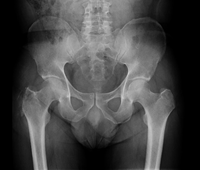

Figure 1 X-ray of the pelvis: Osteolytic lesion at the level of the right greater trochanter.